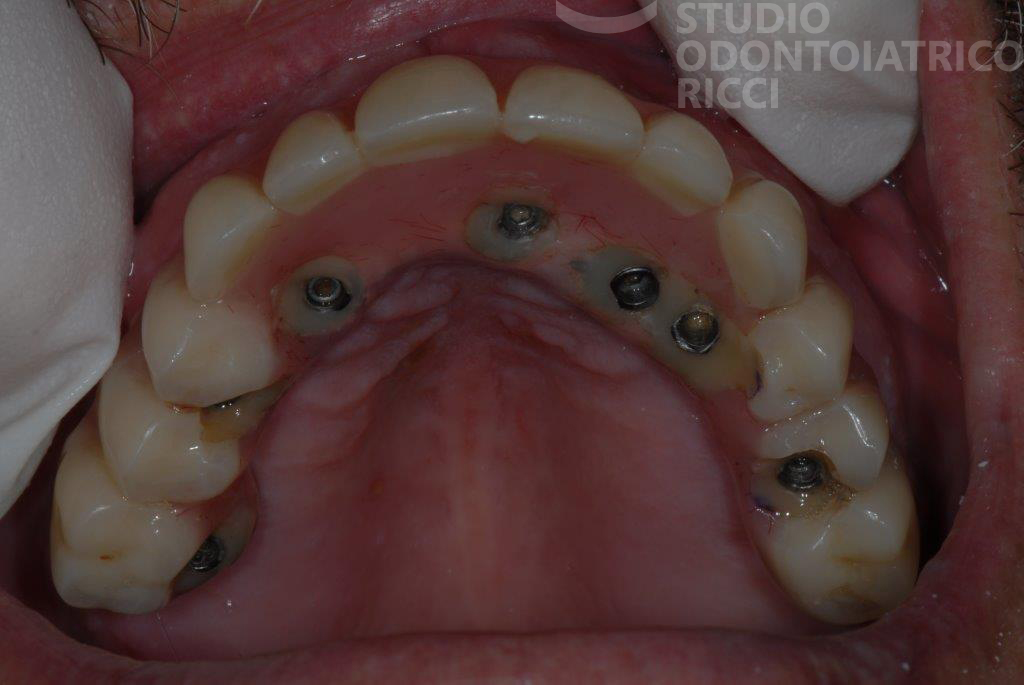

Ponte su impianti, in caso di edentulie parziali

Quando mancano più denti adiacenti, è possibile realizzare un ponte fisso ancorato a due o più impianti, evitando protesi mobili e garantendo stabilità e comfort.